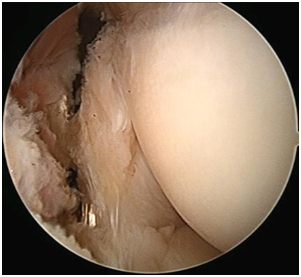

1. Arthroscopic or open65–68 Mini open including Nirschl technique69,70 Long term results of arthroscopic release.71 The arthroscopic release is the commonest form of operative management in our practice (Figures 36).

Figure 5 Arthroscopic view of frayed lateral capsule in Lateral epicondylitis.